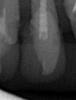

Hope Опубликовано 19 апреля, 2008 Поделиться Опубликовано 19 апреля, 2008 Снимочек к вопросу о нерентгеноконтрастности Градии (помнится, кто-то просил выложить) - 2.1 2.2 Ссылка на комментарий

IgorD Опубликовано 19 апреля, 2008 Поделиться Опубликовано 19 апреля, 2008 в нерерентгенконтрастности, или слабой рентген контрасности материала Градиа - вижу только "+"на недела пришлось снимать несколько грандиозных реставраций с фронтальных зубов, так сделав снимки невозможно было даже примерно определить сколько осталось тканей зубов... и пилить приходилось потихоньку дабы максимально оставить ткани зубов... Ссылка на комментарий